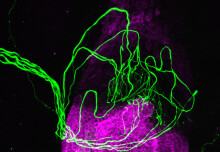

AI breast screening

New AI tool detects up to 13% more breast cancers than humans alone

A new AI tool from Kheiron Medical Technologies and Imperial College London can detect up to 13% more breast cancers than humans in breast screenings.